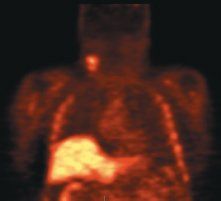

In head and neck cancer, FLT-PET could be used to identify how much marrow has been suppressed after radiotherapy (see Figure). In a study done by Dr. Graham's group at the University of Iowa, the FLT uptake and change early after treatment in squamous head and neck tumors was adequately characterized with SUV obtained at 45 to 60 minutes and correlated well with other post-treatment markers (J Nucl Med 50:1028-1035, 2009).

Top, baseline FLT-PET scan showing radiotracer uptake in right neck nodes and normal distribution of FLT in the bone marrow and liver. Follow-up FLT-PET scan (Bottom and Top Of Article) after 10 Gy of radiotherapy and one cycle of chemotherapy. The uptake in the right neck nodes is decreased. There is also complete disappearance of FLT uptake in the irradiated bone marrow in the cervical spine consistent with marked reduction of cellular proliferation. Images courtesy of Yusuf Menda, MD, and the Universtiy of Iowa department of radiology.